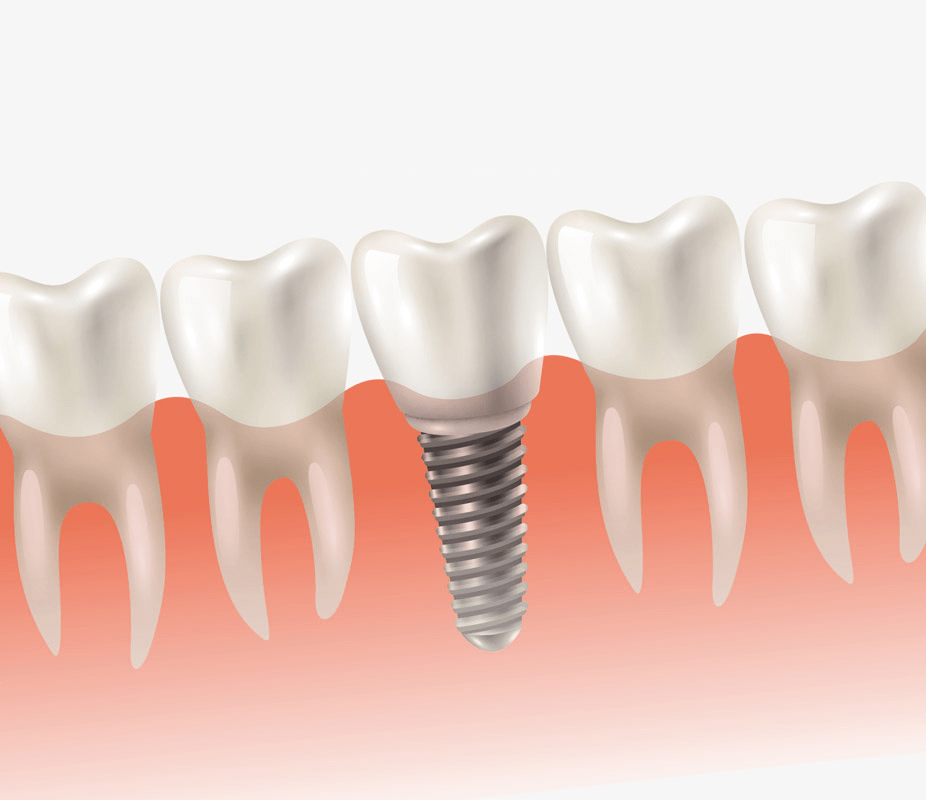

When choosing dental implants in Perth, you are paying for:

- the dental professionals’s extensive training and experience

- the quality material and certification of the implant used and the cost to get approval in Australia

- the level of expertise of supporting staff working with the dentist

- the quality of the parts that attach to the dental implant

- the dental clinic equipment and processes that are of a higher standard

- the extensive level of infection control in dental surgery, which is dramatically superior to overseas clinics